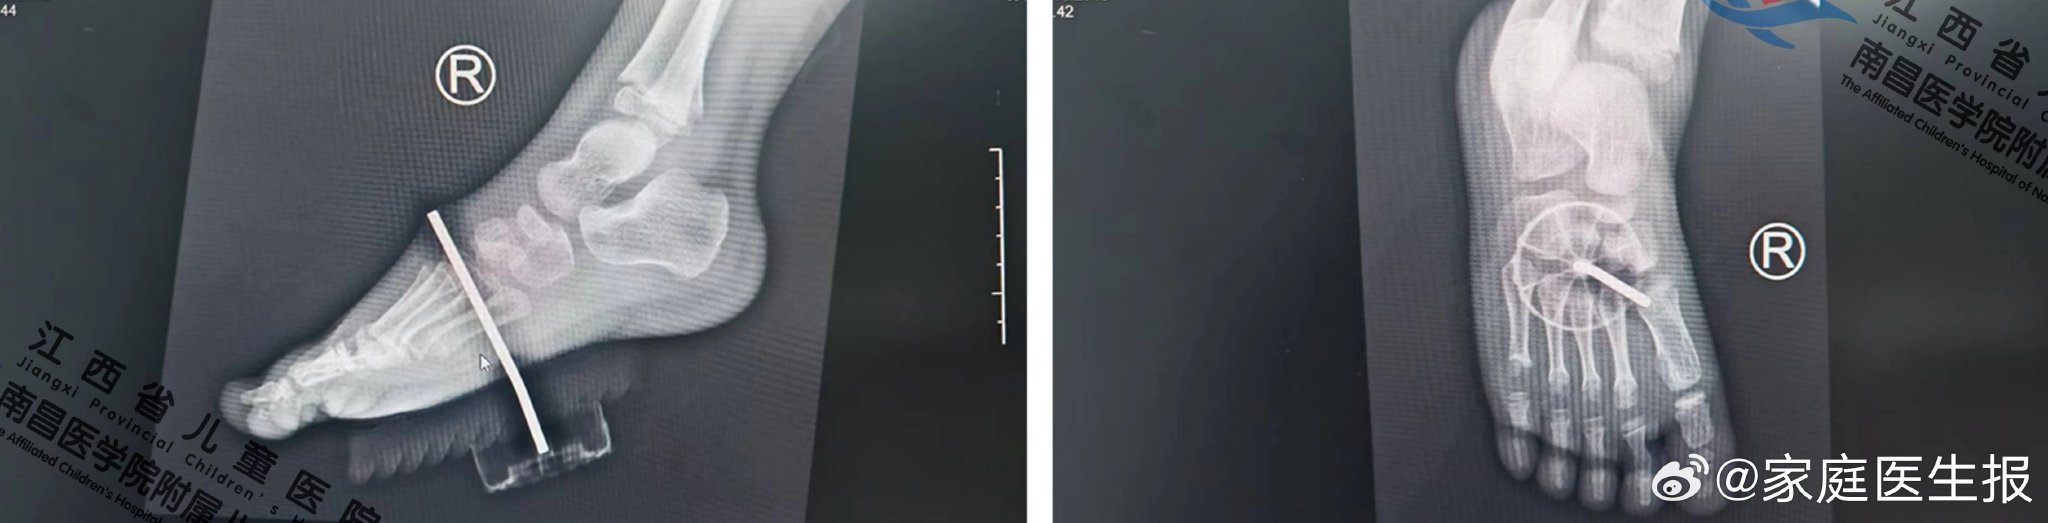

【4岁男童足底被玩具钢钉刺穿,江西省儿童医院骨科团队精准“拆钉”修复】近日,江西省抚州市4岁男童骁骁玩耍时,右脚不慎踩到玩具钢钉,钢钉从足底插入。父母不敢有丝毫耽搁,连夜带着骁骁前来江西省儿童医院急诊外科,入院已是晚上10点。完善相关检查后,急诊外科值班医生综合判定转入骨科治疗。骨科熊飞医生仔细检查骁骁足部,并结合X线片提示,判定为右足损伤并足软组织异物残留,需立即实施手术,否则可能引发感染甚至损......